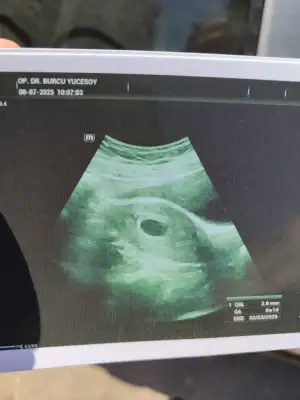

Selamlar teyzoşlar 6 haftalık ilk kontrole gittim hersey yolunda cok şükür kalp atışıda duyduk 6+1 cikti ultrason olcumune gore 🤲🏻 darısı sizlere olsun

• IMG_20250708_101635.webp

IMG_20250708_101635.webp

47,5 KB · Görüntüleme: 84